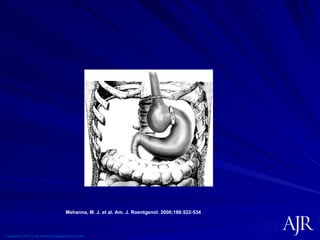

Copyright © 2007 by the American Roentgen Ray Society Mehanna, M. J. et al. Am. J. Roentgenol. 2006;186:522-534